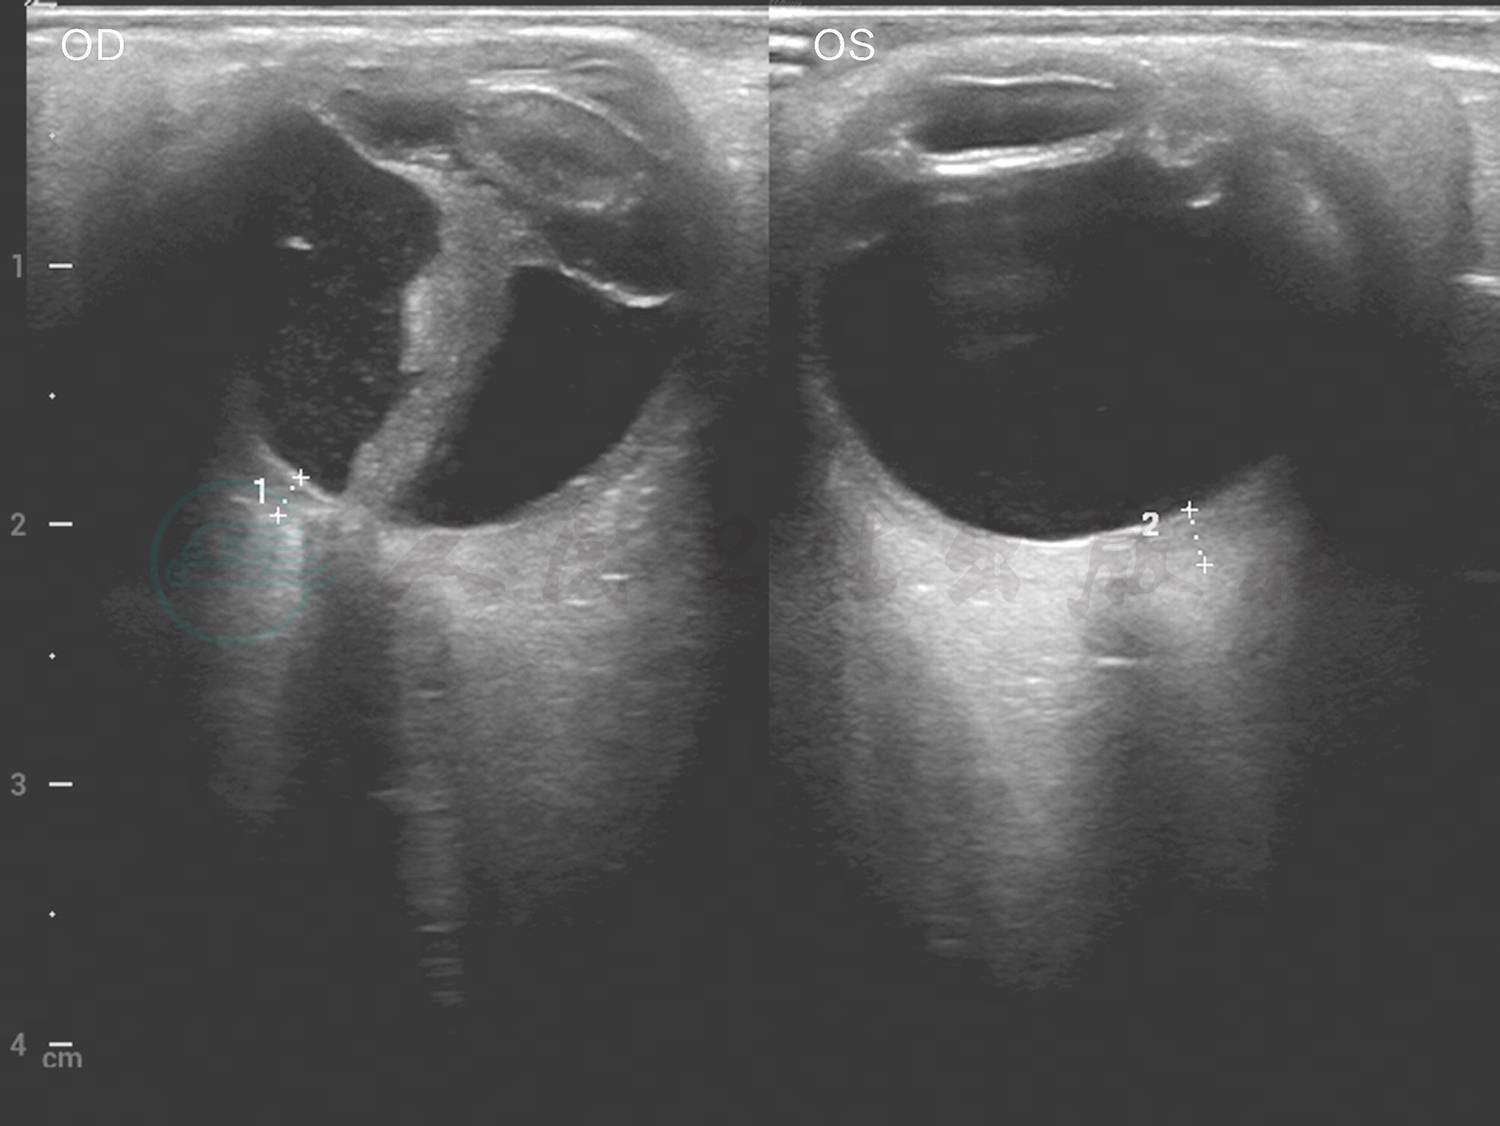

眼B超见左眼玻璃体混浊(图2)。UBM检查见中低回声巩膜隆起(图3)。对右眼巩膜肿物进行穿刺,取其内容物培养未见细菌、真菌等微生物生长。PET-CT见肋部软骨串珠样改变(图4)。

图3 患者门诊就诊时(2020年4月16日)UBM检查见双眼中低回声巩膜隆起

引自:主编:.同仁眼科疑难病例精析:同仁眼科临床病例讨论会1.第1版.ISBN:978-7-117-33030-5